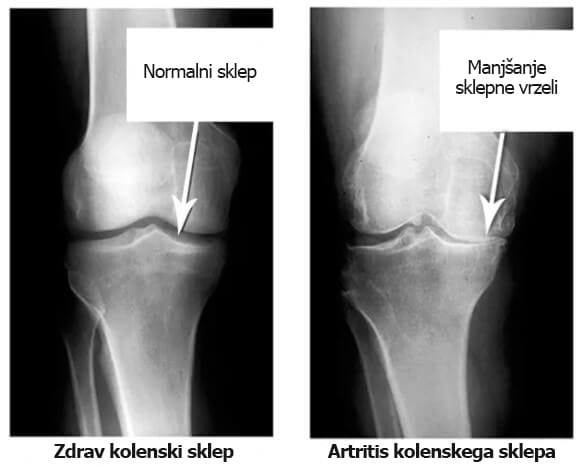

Če pogledamo te rentgenske slike, vidimo, da na desni sliki ni sklepne votline – kosti drgnejo druga ob drugo, kar bolniku povzroča neznosne bolečine. Ta proces je zelo težko zaustaviti!

Koliko časa po vašem mnenju traja, da se stanje tkiva in sklepa tako poslabša, da lahko govorimo o invalidnosti?«